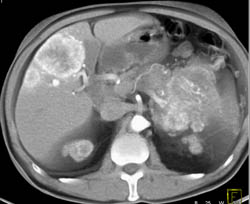

Islet Cell Tumor With Liver Metastases